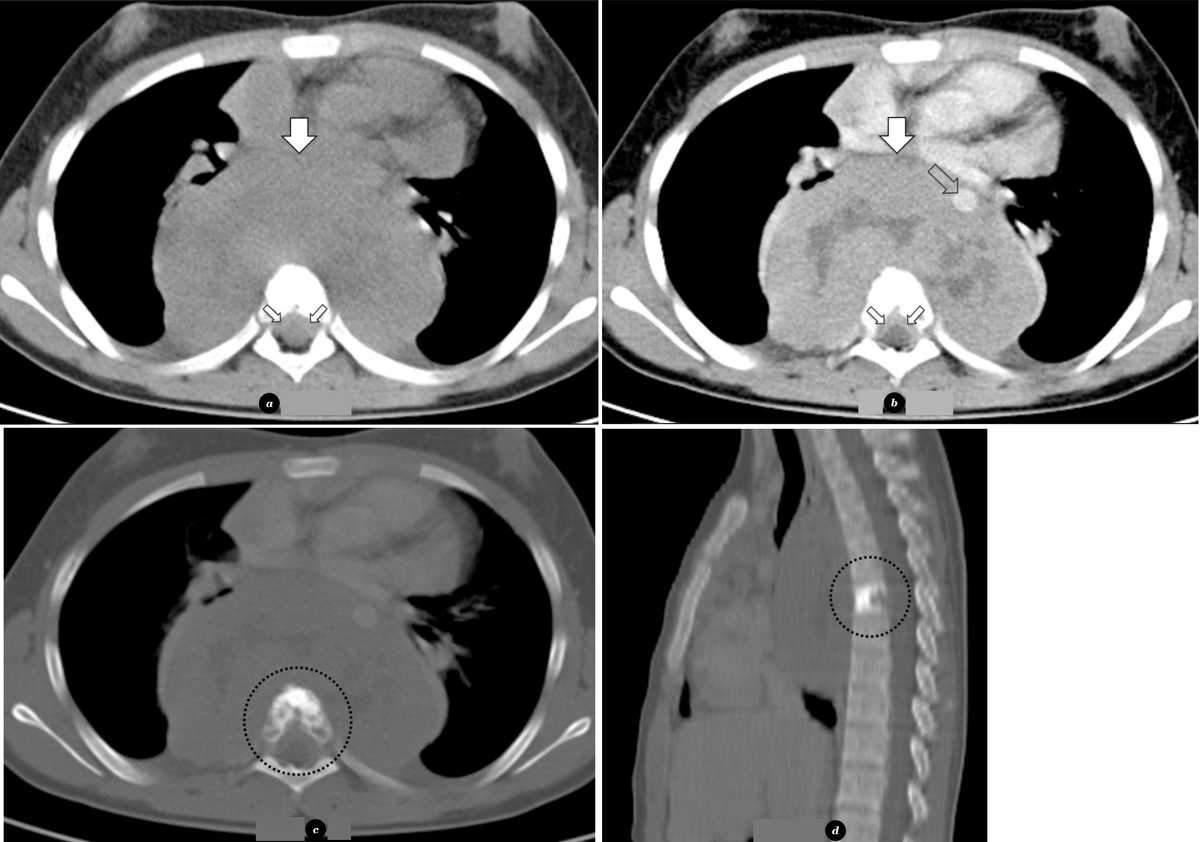

Chest CT revealed a midline well-defined soft-tissue mass with a diameter of 12 cm, located in the posterior mediastinum, adjacent to the vertebral bodies from T3 to T8, encasing the descending aorta (image below). The mass was associated with permeative destruction and osteosclerosis of the 6th thoracic vertebral body (image (d)). There was also extension to the spinal canal through the neural foramina at the 6th to 7th thoracic vertebrae.